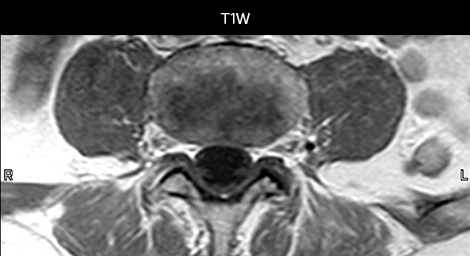

“We use mDIXON TSE extensively in our spine imaging in the emergency room,” says Dr. Karis. “It’s particularly nice in that it is very robust with regard to susceptibility type of problems that would come up with traditional spectral fat-saturated images; these problems are essentially eliminated with the mDIXON technique. In our ED environment it’s really nice to have the fat-free imaging that goes along with the mDIXON technique.

“For the thoracic and cervical spine routine non-contrast exam, for example, we perform one mDIXON T2 TSE sequence, which provides us with two outputs: the fat-and-water-together T2-weighted images, as well as the water-only sagittal T2-weighted images. And then we also perform an axial gradient echo exam.”